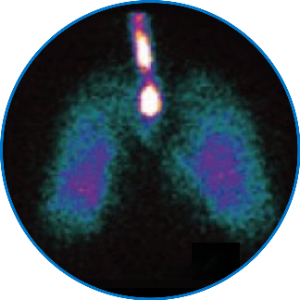

Imagen gammagráfica representativa del depósito pulmonar de aerosol en un paciente que recibe ventilación con presión de soporte (adaptado de Dugernier J, et al. Ann Intensive Care. 2016;6(1):73).6